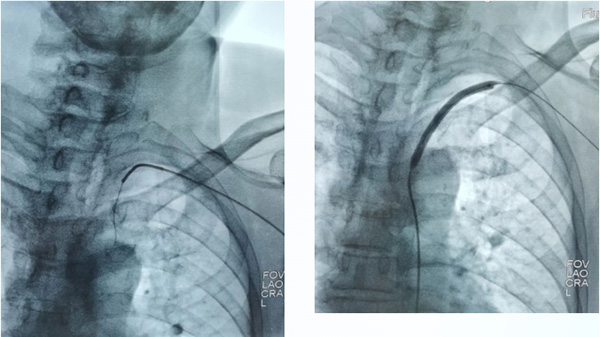

根據(jù)患者情況,神經(jīng)內(nèi)二科和介入導(dǎo)管室制定了詳細(xì)的檢查治療方案,決定為患者進(jìn)行神經(jīng)介入治療——DSA(數(shù)字減影血管造影系統(tǒng))引導(dǎo)左側(cè)鎖骨下動(dòng)脈血管成形術(shù)及支架植入術(shù)。術(shù)中明確左鎖骨下動(dòng)脈閉塞的兩端,開通后予以5mm球囊預(yù)擴(kuò)張,再反復(fù)定位下置入8-37mm支架(支架直徑8mm長(zhǎng)度37mm)置入后造影復(fù)查,顯示病變血管狹窄基本解除,血流通暢。目前患者狀態(tài)良好,對(duì)術(shù)后效果感到十分滿意。